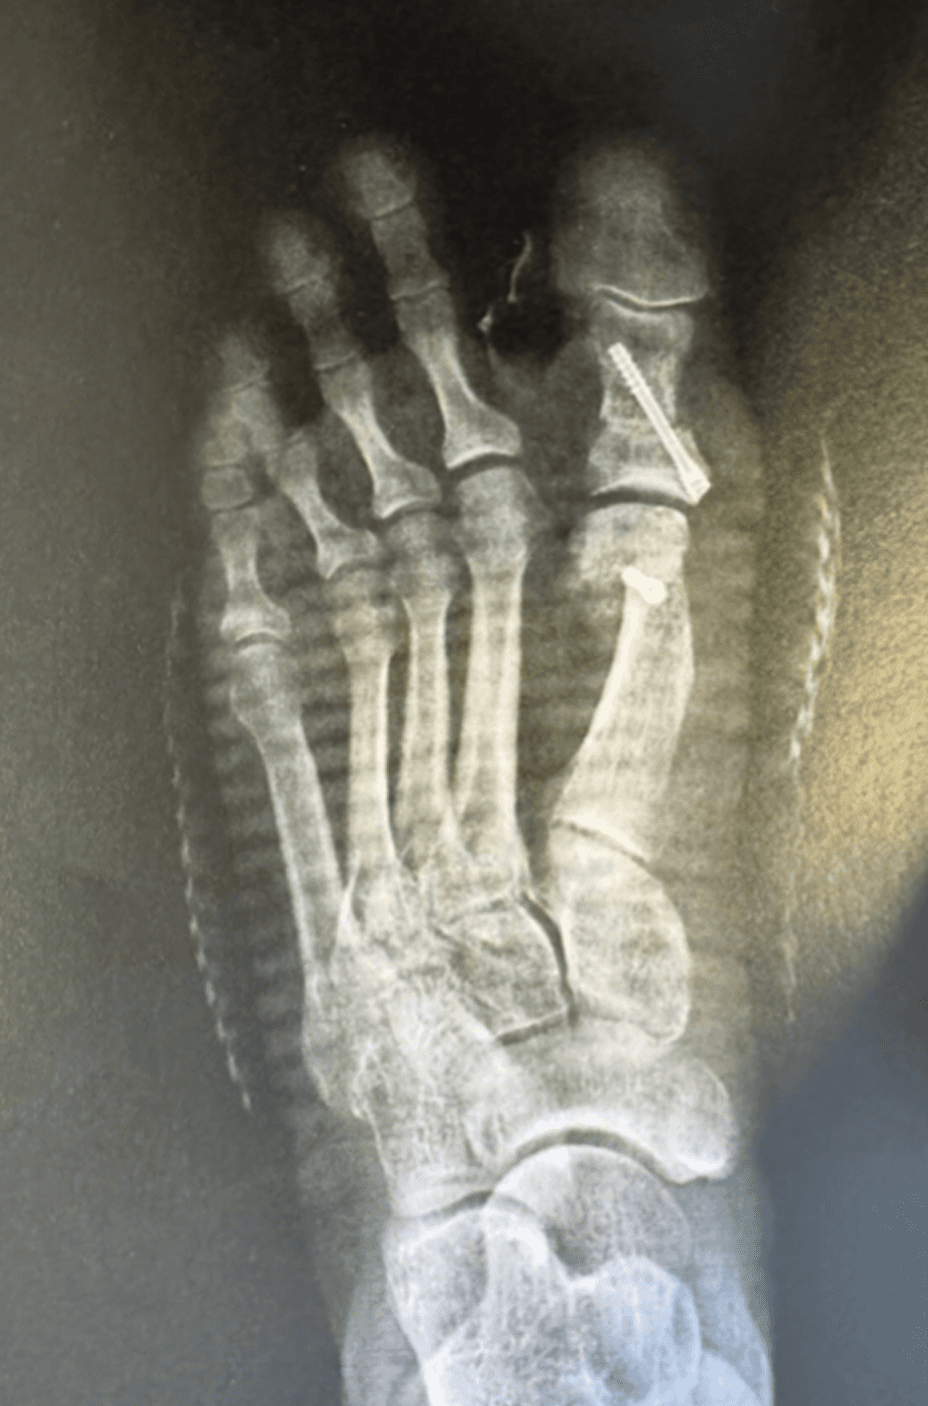

Radio 15 jours après